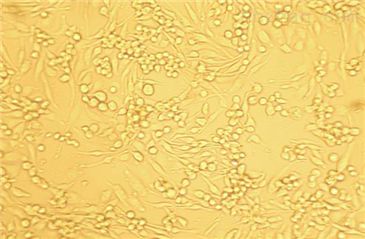

LIM1215

- 生长状态:

贴壁生长

LIM1215(结直肠癌细胞)复苏